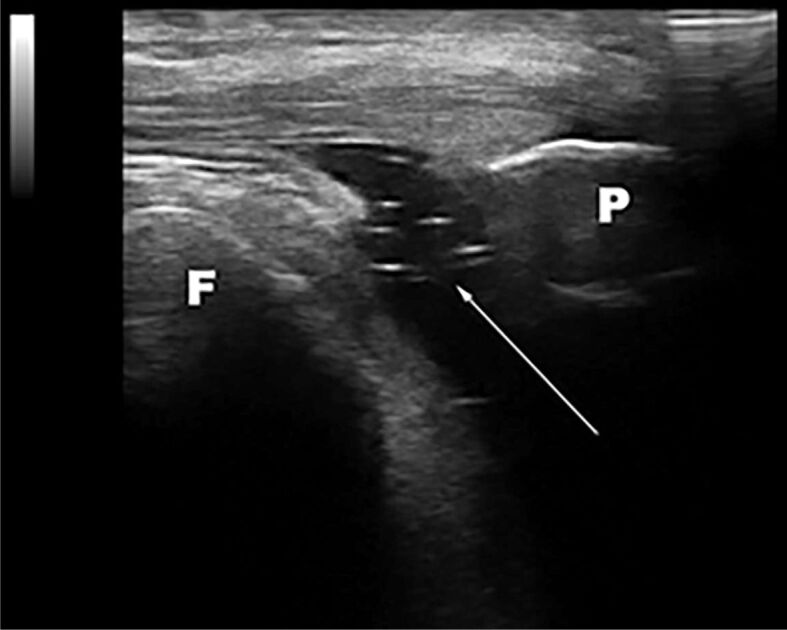

Background: Hyperuricemia is classically defined as serum uric acid (SUA) value higher than 6.8 mg∕dL; between hyperuricemic patients, only 15-20% will develop gout. Our first goal was to find if there is a specificity of the "snowstorm" feature on ultrasound (US) for hyperuricemia. Moreover, we aimed to determine if there is a level of SUA from which the urates tend to appear in the synovial fluid, without generating a typical clinical gouty flare.

Patients, materials and methods: We conducted a cross-sectional, transverse study, including 108 consecutive patients that displayed a set of clinical and imaging features, such as swollen knee and US proof for knee joint effusion.

Results: Performing binary logistic regression, the relation between the explanatory variable (hyperechogenic spots) and the response variable (SUA) was demonstrated to be a significant one (p=0.005). The value of 0.397 for the statistical phi coefficient suggests a medium intensity association between the diagnosis of gout or asymptomatic hyperuricemia and whether the patients have hyperechogenic spots or not. We found the cut-off value for SUA equal to 4.815 mg∕dL, regardless of gender, from which, the urate starts to precipitate. Values for men tend to be higher in comparison to the ones found for women (4.95 mg∕dL vs. 3.9 mg∕dL).

Conclusions: The "snowstorm" aspect of the fluid might be the result of an increased level of SUA and more than this, the cut-off level for SUA to precipitate might be lower than the fore used values.